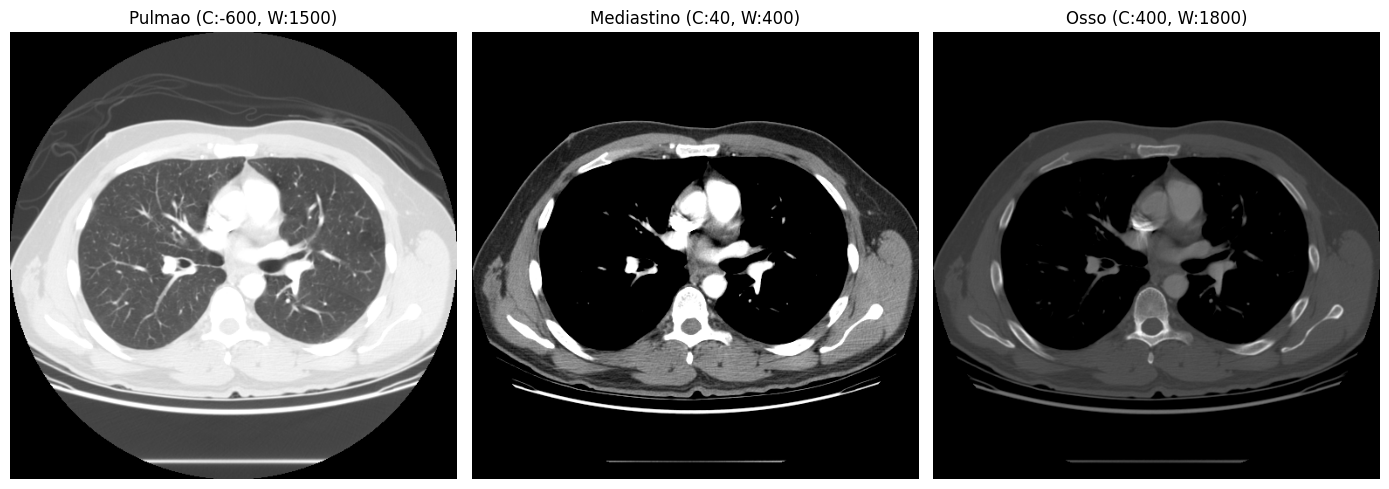

fatia_meio = ct_array[ct_array.shape[0] // 2]

janelas = {

"Pulmao (C:-600, W:1500)": (-600, 1500),

"Mediastino (C:40, W:400)": (40, 400),

"Osso (C:400, W:1800)": (400, 1800),

}

fig, axes = plt.subplots(1, 3, figsize=(14, 5))

for ax, (nome, (center, width)) in zip(axes, janelas.items()):

img = aplicar_janela(fatia_meio, center, width)

ax.imshow(img, cmap="gray")

ax.set_title(nome)

ax.axis("off")

plt.tight_layout()

plt.show()

A mesma fatia, três visualizações completamente diferentes:

- Janela de pulmão (C:−600, W:1500): evidencia o parênquima pulmonar e as vias aéreas

- Janela de mediastino (C:40, W:400): revela tecidos moles, vasos e órgãos

- Janela de osso (C:400, W:1800): destaca a estrutura esquelética